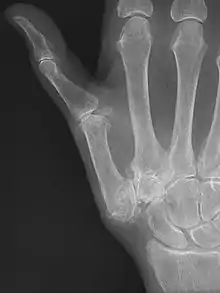

Classification

CMC OA can be divided into different stages which show the progression of the disease. The most commonly used classification is the radiological staging protocol according to Eaton and Littler. Four different stages are distinguished on radiological evidence of synovitis, joint space and capsular laxity.[15][21]

Stage 1:

- "synovitis phase"

- slight widening of the joint space

- articular contours are normal

- < 1/3 subluxation of the joint (in any projection)

Stage 2:

- There is a significant capsular laxity

- 1/3 subluxation of the joint

- Osteophytes, < 2 mm in diameter, are present. (usually adjacent to the volar or dorsal facets of the trapezium)

Stage 3:

- > 1/3 subluxation of the joint

- Osteophytes, > 2 mm in diameter, are present (usually adjacent to the volar and dorsal facets of the trapezium)

- Slight joint space narrowing

Stage 4:

- Major subluxation of the joint.

- Very narrow joint space

- Cystic and sclerotic subchondral bone changes are present

- Significant erosion of the scaphotrapezial joint.